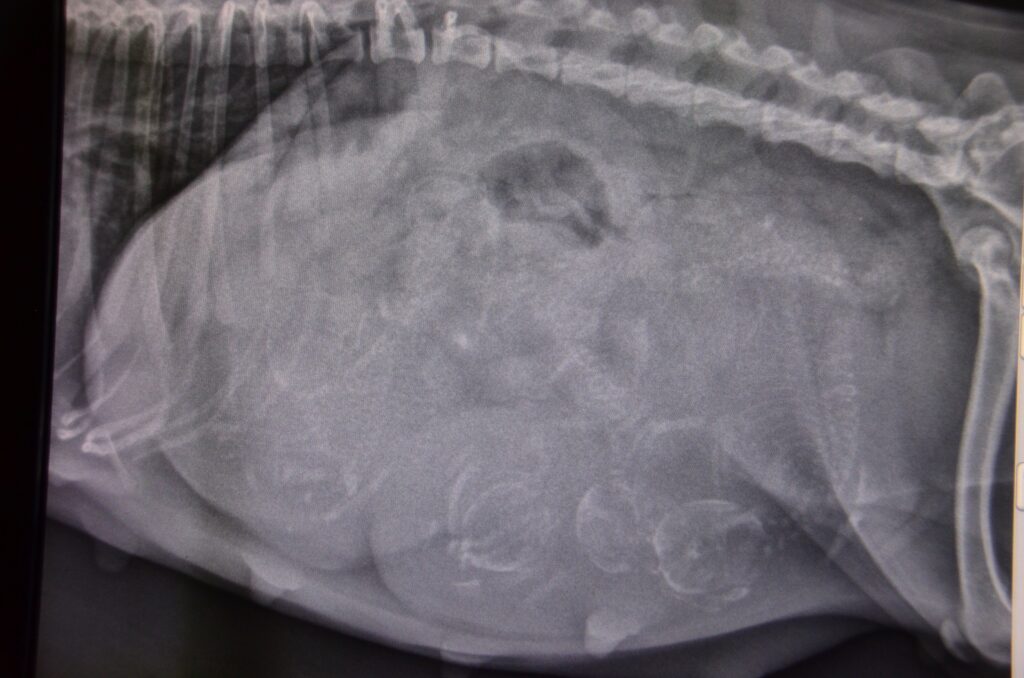

La radiographie est une sorte de « photo » qui permet d’observer les contours du squelette et des articulations mais également des organes de l’abdomen et du thorax en fonction de leur différence de densité au rayons X.

Nous sommes équipés en appareils de radiographie numérique, à Redon et à Saint Gildas, nous permettant d’avoir des éléments d’orientation ou de certitude immédiatement lorsque c’est nécessaire. Grâce aux images de grandes qualités que nous obtenons, nous saurons au mieux vous orienter pour traiter et prendre en charge au mieux vos petits compagnons.